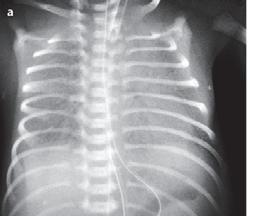

• RTG hrudníku: stadia RDS se odlišují do 4 stupňů (à tab. 1.6)

Tab. 1.6 Klasifikace RDS podle diagnostických radiologických kritérií

stupeň (stadium) radiologická kritéria

stupeň 1 jemná granulární kresba v rozsahu celé plíce

stupeň 2 současně pozitivní vzdušný bronchogram mimo srdeční stín

stupeň 3 současně neostře ohraničený srdeční stín a kontura bránice

stupeň 4 bílá plíce (à obr. 1.5)

Obr. 1.5a Syndrom dechové tísně u předčasně narozeného novorozence, RTG snímek hrudníku po intubaci, který byl provedený za 2 hodiny po porodu: mléčná snížená transparence, vzdušný bronchogram, kontury srdeční a mediastina neostré

nis suis 80 mg v 1 ml suspenze, Chiesi Farmaceutici

S.p.A., Parma, Itálie; držitel registračního rozhodnutí – poznámka překladatele). Po podání surfaktantu dojde ke zlepšení oxygenace a ke zlepšení výměny krevních plynů, snižuje se incidence pneumotoraxu a sníží se i mortalita, která je spojena s RDS a vznikem bronchopulmonální dysplazie.

Indukce plicní zralosti: těhotným se podává 48 hodin před porodem betametazon, který indukuje syntézu surfaktantu ještě před porodem. K tomu je nutné připomenout i význam šetrně vedeného porodu a optimálně prováděné primární resuscitace těchto rizikových dětí.